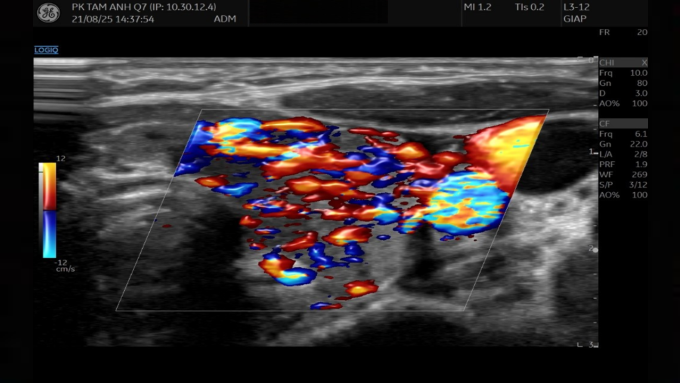

ThS.BS.CKI Hạp Tiến Lộc, khoa Nhi, Phòng khám Đa khoa Tâm Anh Quận 7, cho biết cổ to là biểu hiện của bướu giáp, do tuyến giáp hoạt động quá mức dẫn đến phì đại nhu mô tuyến. Hormone giáp kích thích hệ thần kinh giao cảm, tăng hoạt động tim khiến tim bệnh nhi đập nhanh, tay chân run.

Kết quả xét nghiệm cho thấy nồng độ thyroxine tự do FT4 của bé đến 47.64 pmol/L (bình thường dưới 20). Hormone kích thích tuyến giáp (TSH) giảm còn 0.005 uU/mL (bình thường 0.34-5.6), tức gần như bị ức chế hoàn toàn. Điều này cho thấy tuyến yên đã ngừng kích thích tuyến giáp do nồng độ hormone giáp trong máu tăng cao. Bác sĩ chẩn đoán bé bị cường giáp do bệnh Basedow (Graves) - một bệnh lý tự miễn khiến cơ thể sản sinh kháng thể kích thích tuyến giáp hoạt động quá mức.